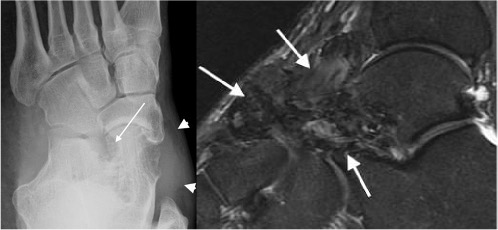

Pigmented villonodular synovitis

- More recently called intra-articular tenosynovial giant cell tumour

- Most commonly seen in young adults

- Characterized by villous nodular proliferation of the synovium with haemosiderin deposition

- Dense periarticular soft tissue swelling with pressure erosion of the subarticular bone

- Joint space preserved until fairly late

- No calcification

- MRI useful to demonstrate the villous nodular synovial masses with low signal haemosiderin on all imaging sequences

PVNS with periarticular soft tissue swelling (arrowheads), bone erosion (arrow) and low signal synovial proliferation on MRI (arrows)